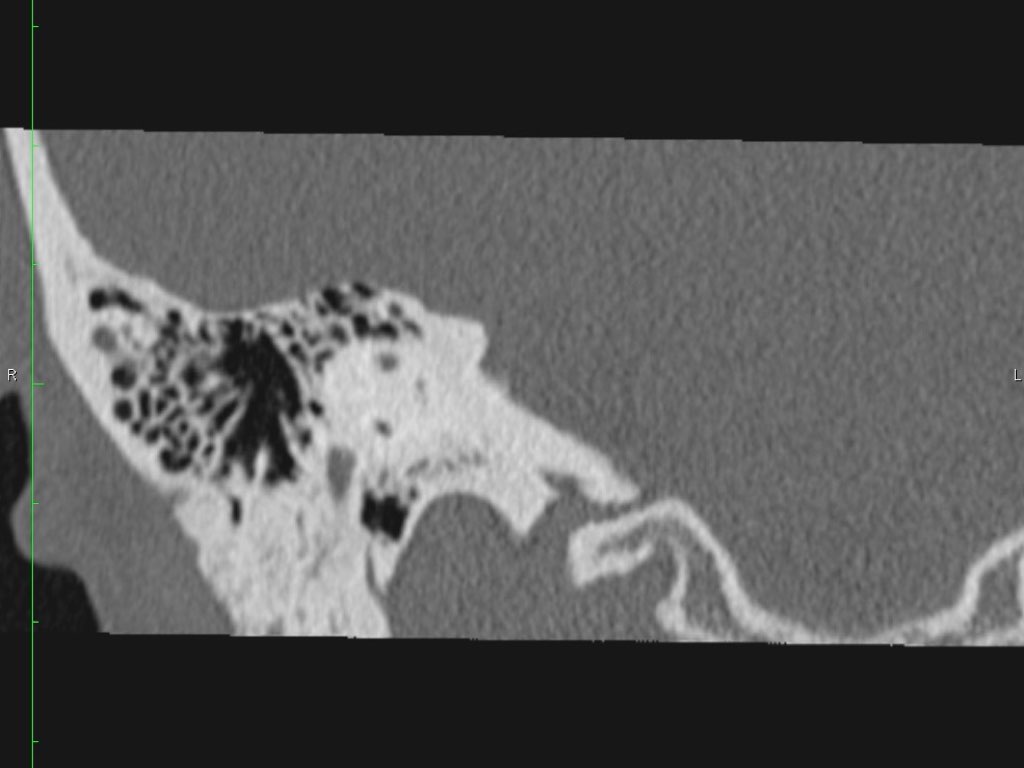

Giải phẫu xương đá trên mặt phẳng cắt ngang (Axial)

Nhấp vào hình ảnh để phóng to.

Cuộn qua các hình ảnh.